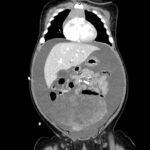

A 5-month-old female presented to the emergency department with worsening abdominal distention and postprandial emesis. Point-of-care ultrasound (POCUS) demonstrated extensive abdominal free fluid with a large, heterogeneous mass in the suprapubic region. This was confirmed on computed tomography (CT) of the abdomen and pelvis. The patient was urgently taken to the operating room for exploratory laparotomy where a ruptured tumor was discovered. The patient was eventually diagnosed with ovarian juvenile granulosa cell tumor. POCUS can be vital in guiding the recognition of rare pediatric conditions in the emergency department and should be considered in patients where there is concern for an acute abdomen.